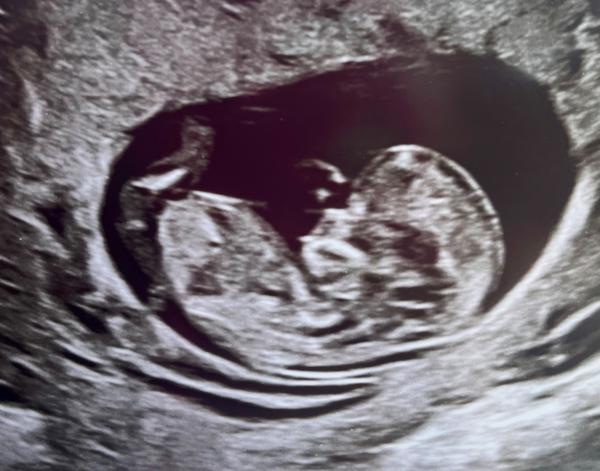

pridávam aj foto